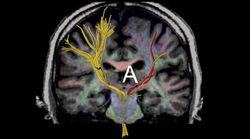

Dr. Hodaie's is a scientist at the Toronto Western Research Institute. Her advanced surgical imaging laboratory focuses on the use of brain imaging to understand changes in brain structure and microstructure in functional neurosurgical conditions. She has a special research interest in the investigation of brain “signatures” of pain and how this can help define better care and personalize treatment for patients. She has published key papers in the area on methodology of small fiber tractography, machine learning models applied to the study of pain, and structural neuroanatomical changes in the gray and white matter in trigeminal neuralgia.

Dr. Hodaie's research specializes in the use of structural brain imaging tools and advanced methods of imaging brain white and gray matter. Her group applies these tools to study functional neurosurgery disorders, including chronic neuropathic pain. These techniques have been used for the imaging of the trigeminal nerves and pathways in trigeminal neuralgia, a most severe facial neuropathic pain condition. Dr. Hodaie is an international expert in the diagnosis and treatment of trigeminal neuralgia and has performed over a thousand surgical procedures for the disorder. Her innovative research has significantly changed our understanding of trigeminal neuralgia pain, and have helped shift the focus from the traditional view of studying the blood vessels compressing the trigeminal nerves, to one that studies nerves and brain abnormalities and how these relate to pain.